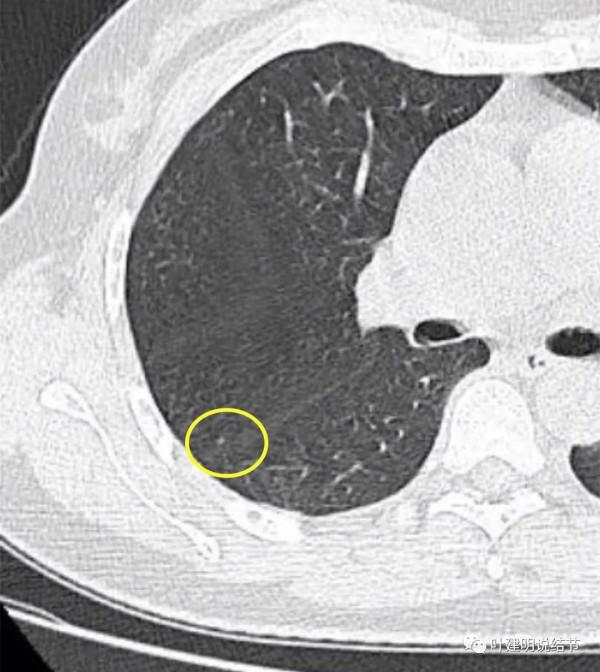

金華的某A,是我同學的大姨子,前段日子因為同學的愛人查出肺結節是早期肺癌,所以她姐姐記起來2年前也查出有肺結節,但沒有複查過,怕也得肺癌,所以到我門診來複查。我們先來看她平掃的CT影象:

從平掃看,病灶雖然小,但就不舒服,極可能是惡性的。我們再來看她其餘部位還有小結節: